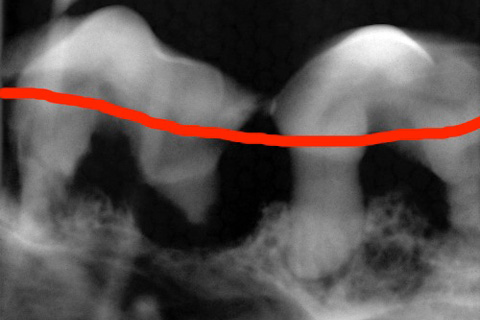

ハグキが溶けてしまっています。本来赤い線のところまでハグキです。

歯のレントゲン写真

その1(軽い所見)

大きい歯の方が健康で、小さい方の歯の骨が黒く溶けています。

赤い線がハグキの線です。